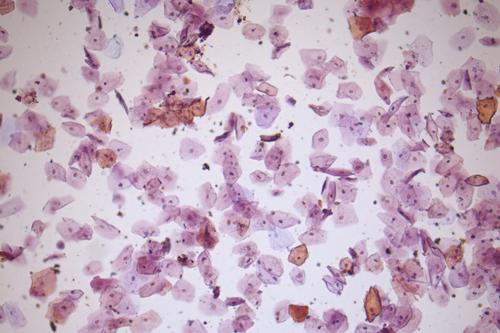

Based on differences in shape, size, appearance, and origin, it is possible to define three types of epithelial cells in urine. The most important ones are renal tubular cells (renal cells), which are an indicator of kidney health. The largest type, squamous cells, comes from the urethra and vagina. Their number is higher in women's urine. The third type, transitional cells (bladder cells), is typical for the urethra and renal pelvis of older men.